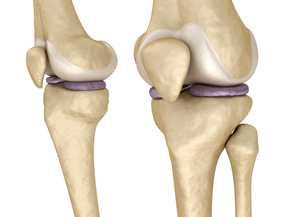

The St. Luke's cartilage preservation and restoration program is dedicated to the treatment of patients with symptomatic cartilage damage, including isolated cartilage defects, meniscal injuries and early arthritis. Our expert physicians will evaluate and recommend treatment options to match the physical demands of each patient's lifestyle.

Our philosophy is to repair the cartilage damage by treating the whole patient and determining the underlying causes of damage, which can include malalignment, ligament instability and loss of meniscal function. We'll also educate patients on the safest and latest treatment options to help them to make the most informed decision regarding their cartilage damage. Conservative, or nonsurgical, management is usually attempted before more invasive, surgical options are considered.

Non-Surgical Approaches to Cartilage Repair and Preservation

Surgical Approaches to Cartilage Repair and Preservation